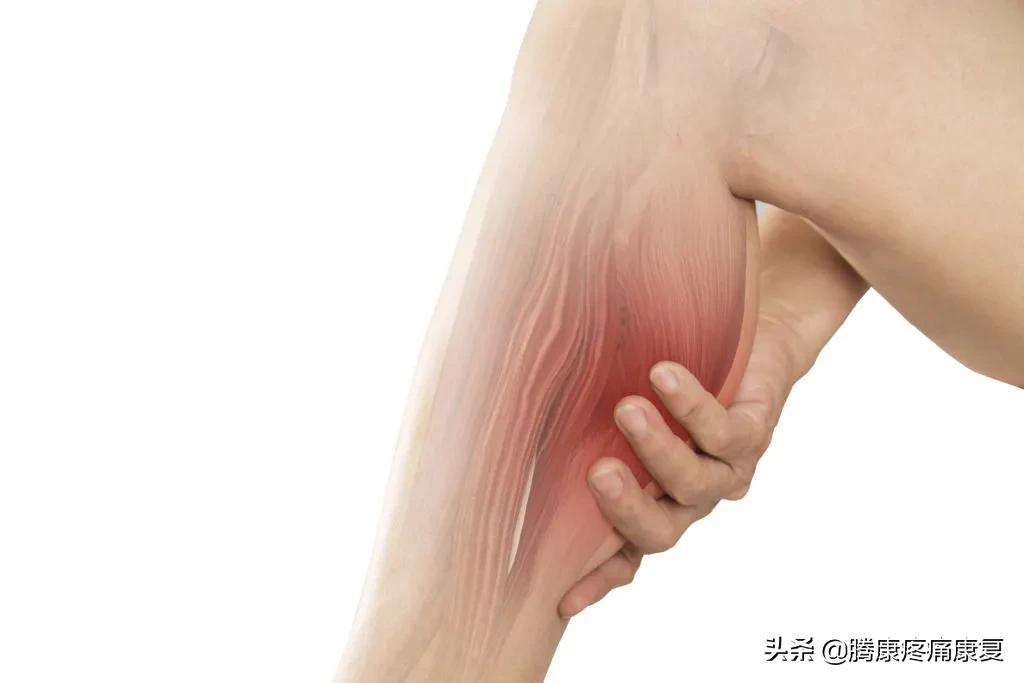

小腿肌肉痉挛

小腿肌肉痉挛是指一块或多块小腿肌肉突然、不自主地收缩,这种现象被称为腿部痉挛(charley horses)

大约60%的成年人在夜间体验过腿部抽筋,平均每次持续9分钟,之后,小腿肌肉可能会疼上好几天。

小腿肌肉抽筋会非常紧张和疼痛,甚至会有明显的结或抽搐感。但我们仍不清楚是什么原因导致了这些问题:

• 小腿抽筋可能与高强度运动后的肌肉疲劳有关。